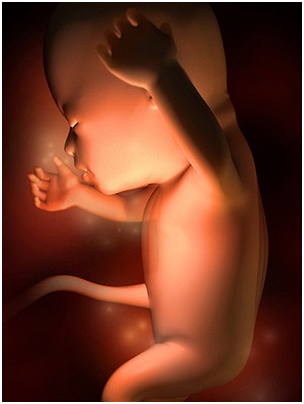

怀孕第34周此时胎儿已经为分娩做好了准备,将身体转为头朝下的姿势。你最近会感觉有一点儿累,这...

怀孕第34周此时胎儿已经为分娩做好了准备,将身体转为头朝下的姿势。你最近会感觉有一点儿累,这... -